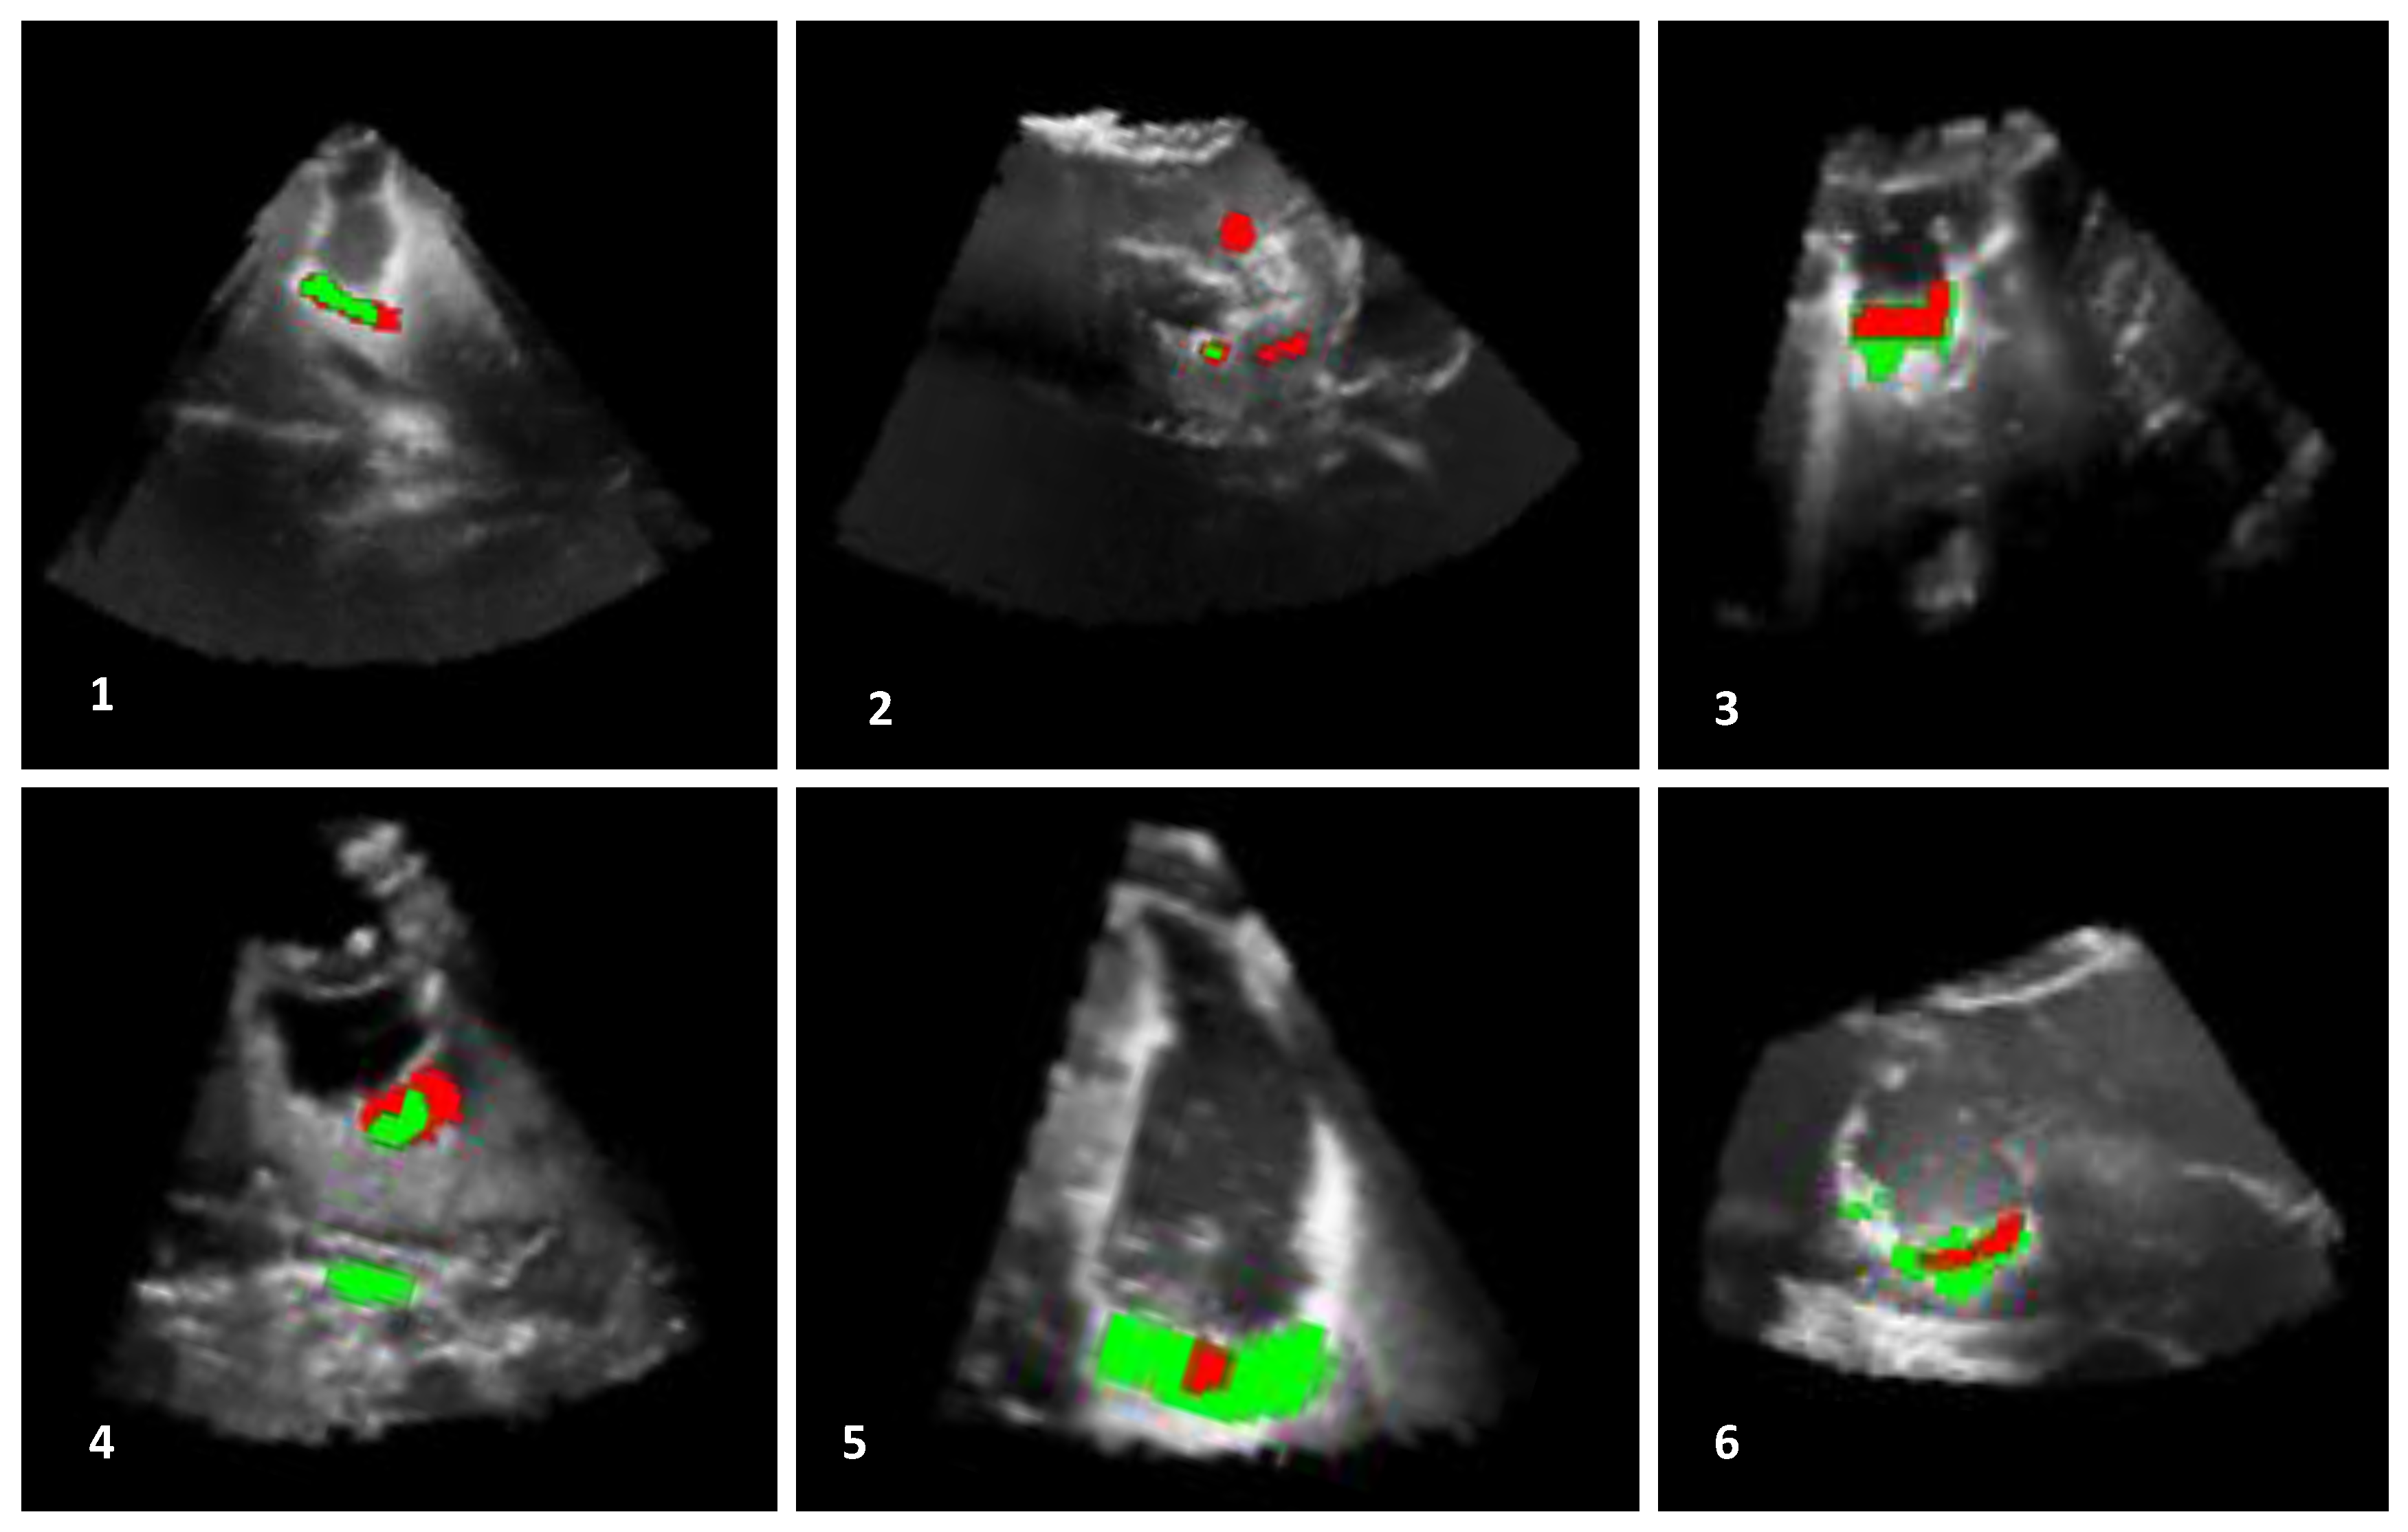

The outcomes, obtained by the automatic proposed method, are presented in Figure 7, Figure 8 and Figure 9. In addition, the algorithm results (in green) and the ground truths (in red) are overlaid on a selected slice of the 3D iB-mode images for visualization purposes. Table 2 summarizes the qualitative and quantitative evaluation. The former is based on expert observations, and the latter is performed by using the overlap, accuracy, area under the curve and error rate measures. The experiments showed that our approach succeeded in detecting the position of all tumor remnant areas in 15 out of 19 patients (). For these cases, a qualitative coding of 1/−1 (all tumorous regions were detected) or 1/1 (all tumorous regions were detected and extra suspected regions, as well) was observed. Regarding the four unsuccessful cases, the areas with tumorous tissue were partially detected in two patients (Patients 2 and 7, where ), and the algorithm failed in the two other cases (Patients 14 and 18, where ). One failure reason is the position of tumor residuals near the image top (Patients 7 and 18). These areas are removed in the preprocessing steps to eliminate artifacts caused by the US probe. The method was also tested on patient data from the set B where false positives were detected in the cases of Patients 20 and 23 and none for Patients 21 and 22.

Figure 7.

Results of residual tumor identification from Patients 1 to 6. The results obtained with the proposed automatic method (in green) and in the manual segmentation (in red) are overlaid on a selected slice of the 3D iB-mode image data. The algorithm missed tumorous structures in Patient 2 and identified extra regions in Patient 4.

Figure 8.

Results of residual tumor identification from Patients 7 to 12. The results obtained by using the proposed automatic method (in green) are superimposed with the expert manual segmentation (in red). The algorithm missed the detection of other tumorous structures in the case of Patient 7, and it identified a large region in the case of Patient 10.